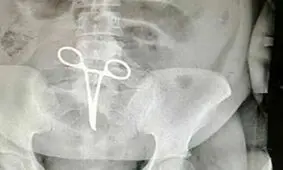

رئیس بیمارستان شهید بهشتی اردستان گفت: اشتباهی که در بیمارستان اردستان اتفاق افتاده است یکی از موارد نادر پزشکی است که…